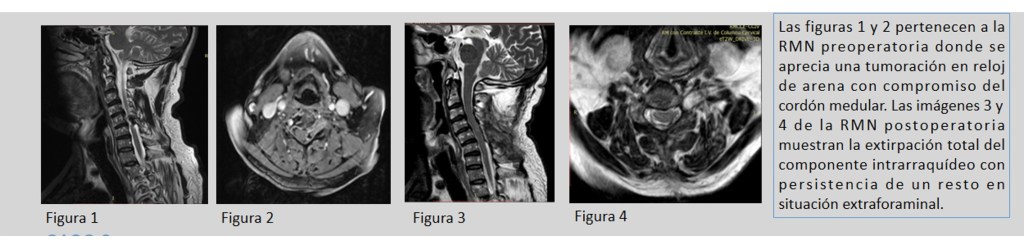

- En cuanto a los tumores que afectan a las cubiertas o elementos de sostén de las estructuras neurológicas, los más frecuentes son los meninigomas, derivados de las capas meningeas que recubren la médula espinal, asi como las schwannomas o neurinomas originados en las células de sostén de raices nerviosas. En ambos casos puede tener lugar la compresión de la médula espinal que provoque la pérdida de función de la misma con el desarrollo de una pérdida de sensibilidad y/o movilidad, asi como posible alteración del control de los esfínteres. Para su tratamiento contamos con la posibilidad de monitorización neurofisiológica intraoperatoria y Microcirugía.

-Tumores espinales: Dan lugar a una gran variedad de situaciones debido a que pueden afectar a diferentes compartimentos: óseo (tumores primarios ó metástasis con o sin extensión al canal raquídeo; siendo los hemangiomas los más frecuentes), intradural-extramedular (los más frecuentes meningiomas y algunos neurinomas) e intradural-intramedular (astrocitomas y ependimomas). Suelen manifestarse con dolor, alteración de la sensibilidad y/o fuerza en las extremidades acompañada o no de alteración esfinteriana. Van a precisar cirugía en caso de que generen inestabilidad vertebral, déficit neurológico o muestren un comportamiento agresivo.